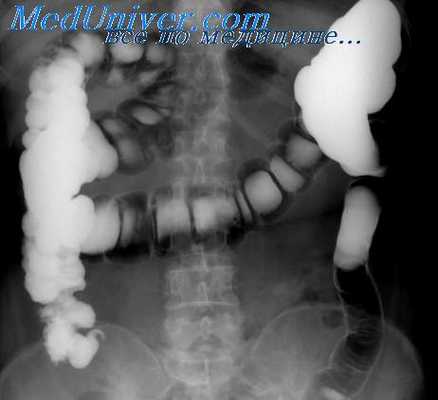

Рак слепой кишки встречается часто, растет, как правило, экзофитно, легко изъязвляется. Долго не нарушает проходимости кишки, имеющей широкий просвет и жидкое содержимое. Хорошо пальпируется. Клинически проявляется поздно, вызывая боли, похудание, анемию. Лишь при локализации опухоли в области подвздошно-слепокишечной заслонки возникают признаки частичной кишечной непроходимости. При рентгенологическом исследовании на одной из стенок кишки обычно выявляется крупный различной формы дефект наполнения с неровными, нечеткими контурами и бугристой поверхностью. Иногда опухоль циркулярно охватывает всю кишку. В центре опухоли нередко обнаруживается изъязвление. Стенка кишки в зоне поражения ригидна, складки слизистой оболочки на границе с опухолью разрушены.

Опухоли больших размеров могут выполнить весь просвет слепой кишки и обусловить симптом ее «ампутации»: подвздошная кишка, которая, как правило, в процесс при этом не вовлекается, непосредственно переходит в высокорасположенный «конец» толстой кишки. Истинная причина этой рентгенологической картины легко устанавливается при раздувании кишки газом, особенно при исследовании в латеропозиции на левом боку. Редко встречающиеся в слепой кишке эндофитные опухоли вызывают циркулярное сужение ее просвета и ригидность стенок, что отчетливо видно при исследовании в условиях двойного контрастирования.

Наибольшую информацию для диагностики доброкачественных опухолей получают при рентгенологическом исследовании кишки в условиях двойного контрастирования и искусственной ее гипотонии. Контрастную взвесь и газ целесообразно вводить в тонкую кишку через дуоденальный зонд, а в толстую — с помощью клизмы. Однако рентгенологически определить вид доброкачественной опухоли, как правило, не удается.